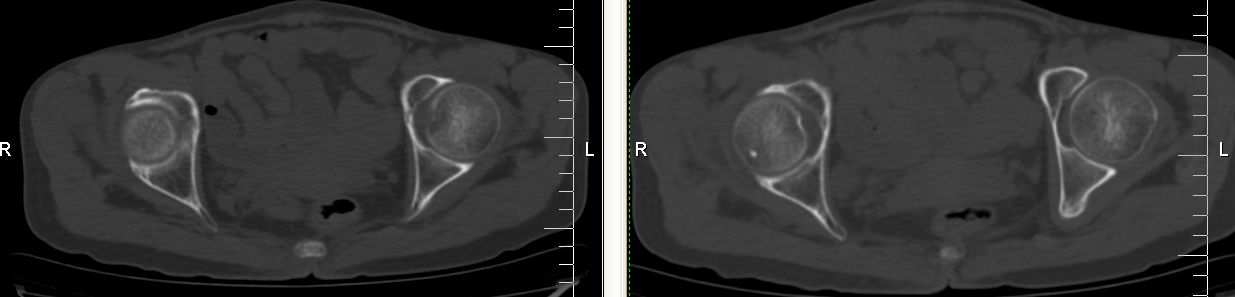

以下是引用余辉在2007-12-5 17:25:00的发言:[br]右侧股骨颈及粗隆区略显膨胀,密度增高略呈不均匀毛玻璃样改变,骨皮质毛糙,考虑1骨纤2骨髓瘤3转移瘤,建议上传软组织窗